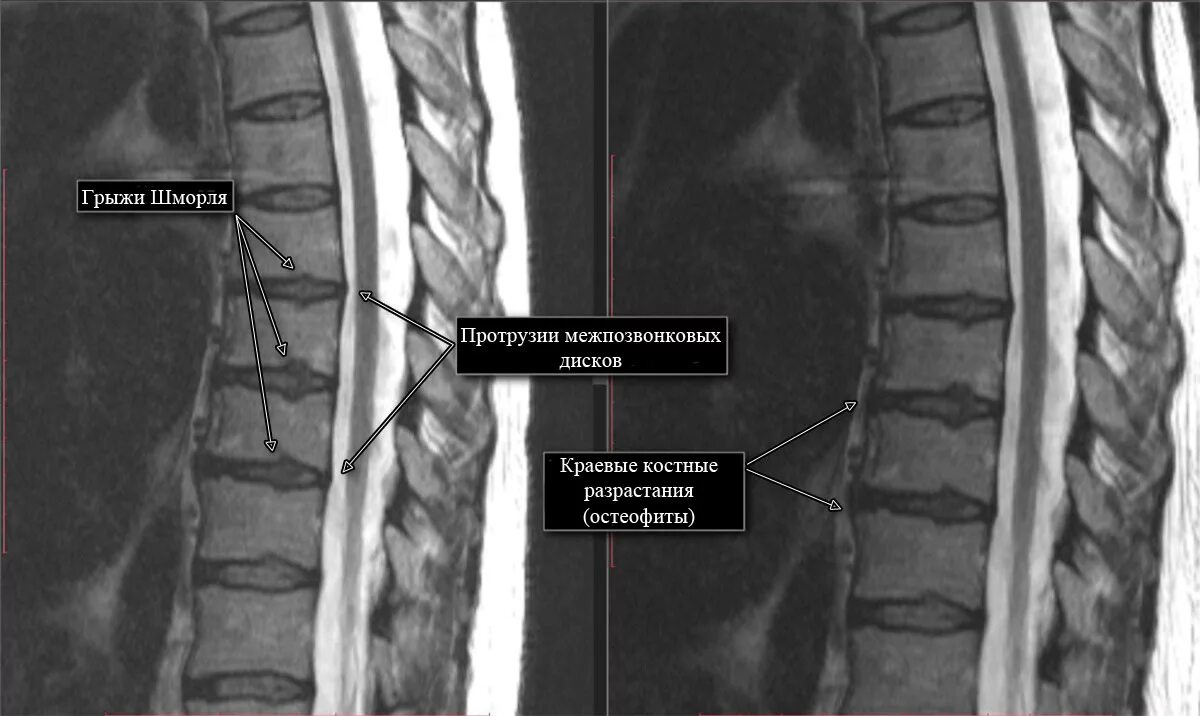

Грыжа диска 3